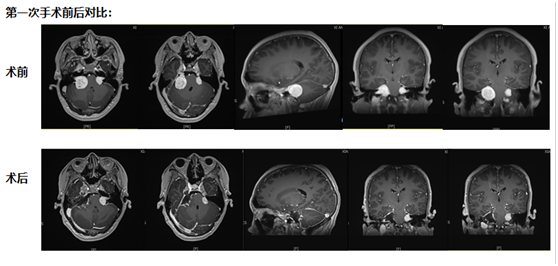

第一次手術:從耳后開口,既要拆瘤又要保聽力

“必須馬上手術!”團隊討論時,周教授分析,“現在腫瘤已經壓到聽力和平衡神經了,再等1個月,負責聽力的神經可能就徹底壞死,到時候再切腫瘤,耳朵也聽不見了?!?span style="display:none">ZCJ28資訊網——每日最新資訊28at.com

考慮到小倪才21歲,團隊沒選 “一刀切” 的方案,而是決定從耳后開一個約10厘米的小口 ——這個位置能精準摸到耳朵旁邊的腫瘤,還能盡量避開控制聽力、面部活動的神經。

手術當天,醫生在顯微鏡下一點點 “剝” 腫瘤:剝到腫瘤深處時,醫生發現再往里切,必然會傷著聽力神經?!巴?這里留一點點,先保聽力?!眻F隊果斷調整,把能安全切除的腫瘤全清干凈,再仔細止血,避免術后出血。